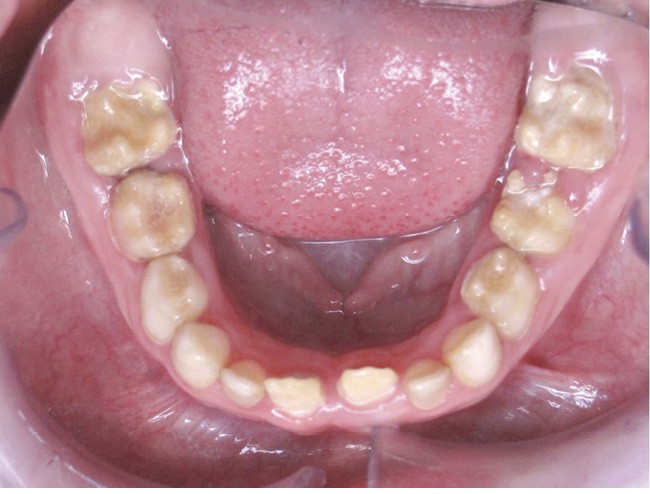

Il existe des anomalies dentaires (tabl. I) [1-12], mais aussi occlusales associées aux AI (fig. 1 et 2).

Selon de nombreuses études, l’anomalie occlusale la plus fréquemment retrouvée en association avec les AI est l’infraclusion antérieure, puisqu’elle est retrouvée chez 22 à 64 % des patients présentant cette affection, et encore plus chez les femmes [2,8,13-19]. Cette anomalie touche tous les types d’AI mais à des degrés très divers. Son incidence semble élevée dans les formes hypominéralisées, moindre dans les formes hypoplasiques et nettement moindre dans les formes hypomatures [8,17,18]. La sévérité de l’atteinte amélaire ne semble pas corrélée avec la présence ou l’intensité de cette malocclusion [17].